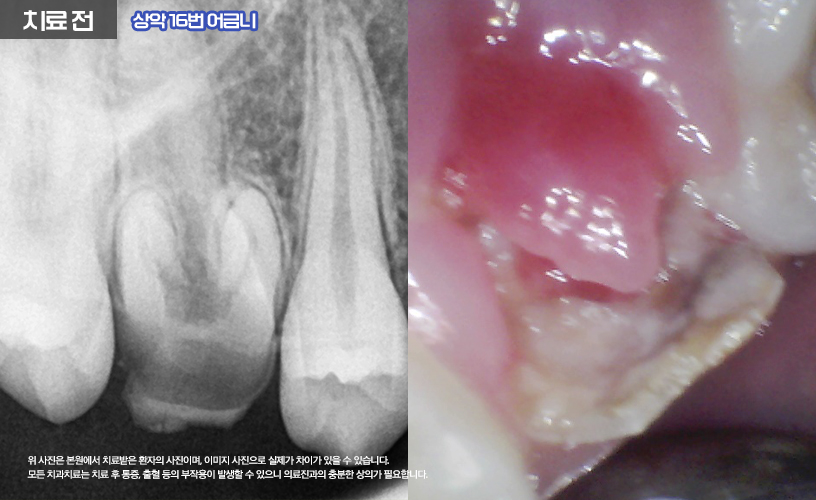

나머지 상, 하악 16,26,36,46번 치아는

신경치료를 통해 치료가 진행됩니다.

먼저 충치로 인해 파절의 정도가 심한 상태이기

때문에 신경치료와 함께 포스트+레진 코어를 통해

얼마 남지 않은 치아의 기둥을 세워

튼튼하게 잡아주었습니다.

또한 환자분의 경우 우식이 깊은 상태였기 때문에

치관의 모양이 상실된 상태에서 우식이

치은연하(잇몸 아래)으로 진행되어

신경치료 전 치은 절제술까지 함께 진행되어

치관의 길이를 확보하는 시술이 추가되었습니다.